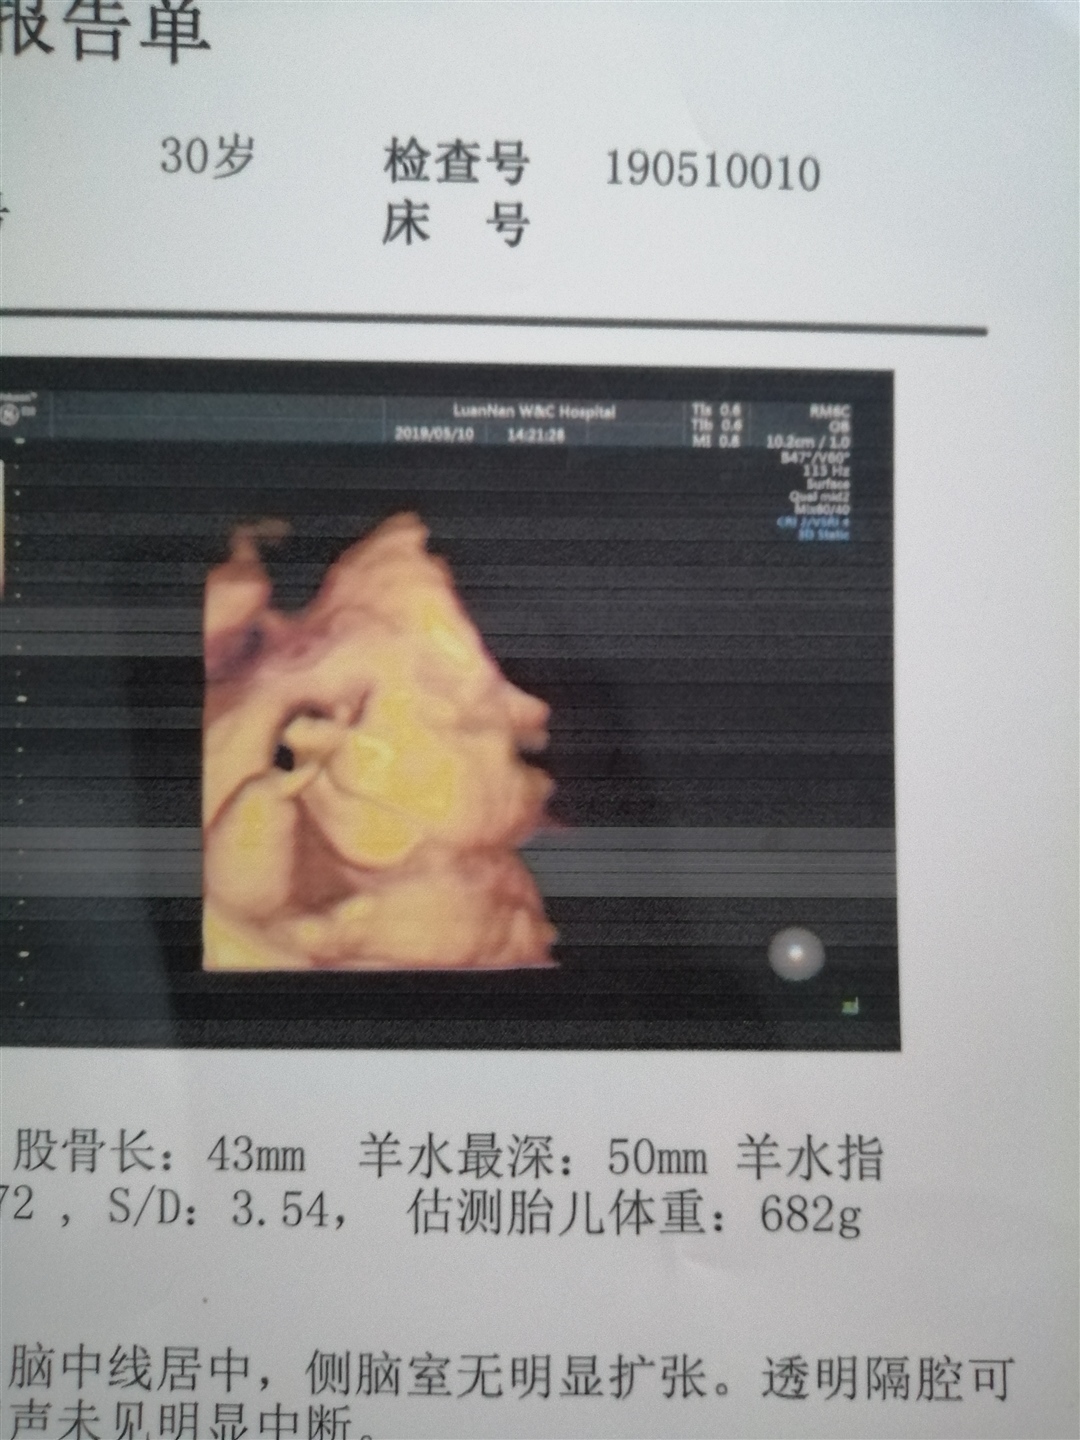

孕32周+5天